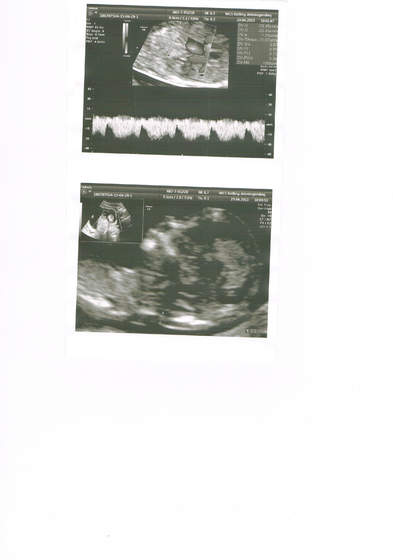

Trochę poczekaliśmy bo mój lekarz robił cc, wziął mnie na usg genetyczne (mąż był ze mną) no i wszystko jest super, dzidziuś zdrowy

Z usg wychodzi 13 tydzień 4 dzień. Kolejne usg gdzieś w 20 tygodniu...

No i syn będzie...

A to nasz.. chłopczyk. Nie potrafię inaczej tych fotek ze skanera wrzucić.